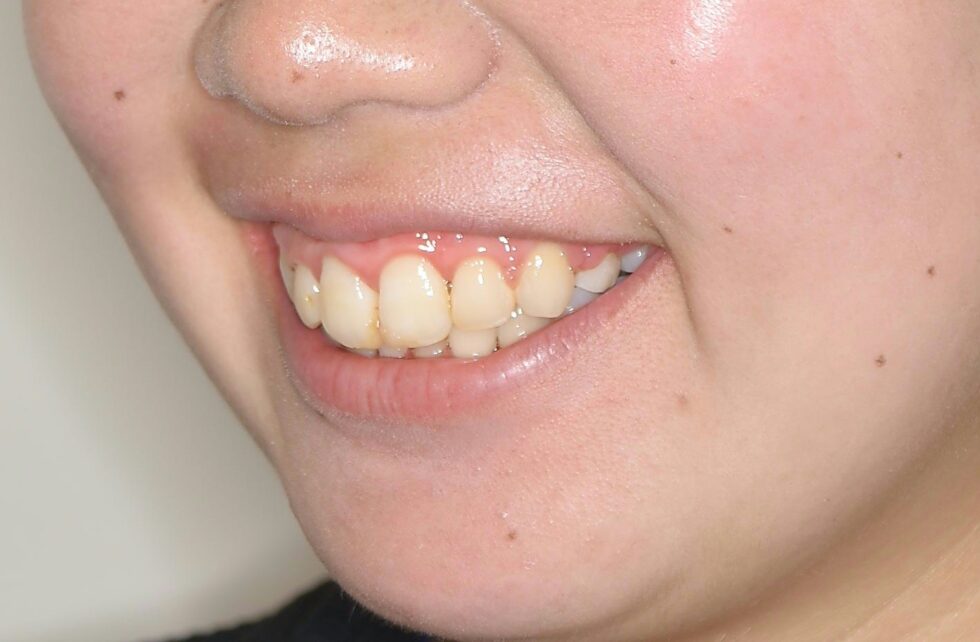

初診時年齢18歳の女性。叢生を伴う上顎前突のケース。

前歯の突出と乱れを気にしておられました。マルチブラケット装置を使用して、上下顎左右側小臼歯の抜歯による動的治療を行いました。突出していた前歯を後退し、乱れも改善することが出来ました。動的治療期間は2年10ヶ月間